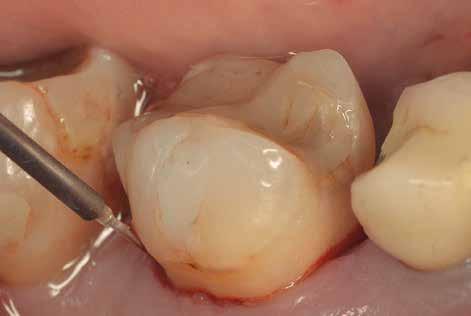

A kezelés e szakaszának a befejezésekor a gyulladásos tünetek hiánya, a csökkenő tasakmélység és a szondázást követő vérzés megszűnése megfelelő bizonyítékul szolgálhat az eddig elvégzett beavatkozások hatékonyságára (15. ábra). A páciensek idővel képesek lesznek ennek az állapotnak a fenntartására, ha a fogorvosok által adott instrukcióknak megfelelően végzik a napi szájhigiénés tevékenységüket, és ha ebben megfelelően támogatják őket.

Ebben a fázisban alapvető fontosságú, hogy bemutassuk a páciensnek a kezelés során elért eredményeket, mivel ezzel tudjuk őt leginkább arra motiválni, hogy fenntartsa az elért, megfelelő szájhigiéniás állapotot, továbbá, hogy rendszeresen megjelenjen a jövőben tervezett kontrollvizsgálatokon. A megfelelően kivitelezett LAFMD protokoll befejezésekor, a páciensünk is megfigyelheti, hogy sem gyulladásos tüneteket, sem vérzést nem tapasztal, valamint érezheti a lágyrészek stabilitásából és a megfelelő szájhigiéniás státuszból fakadó előnyöket (16. ábra). A Condor intraorális szkennerel készített színes, háromdimenziós modellek kiválóan alkalmasak a szájüregi státusz bemutatására, továbbá a páciens hatékony motivációjának elősegítésére.